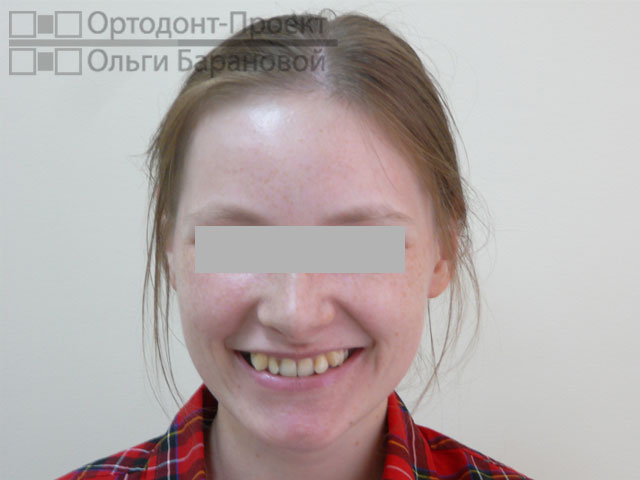

Проблема: к ортодонту О.А. Барановой обратилась молодая девушка с жалобами на то, что криво растут зубы.

Решение: выполнено лечение с удалением зубов, наиболее эффективное в данном случае. Для лечения использованы металлические брекеты Damon.

Ортодонт О.А. Баранова провела осмотр и рассказала о возможностях ортодонтического лечения. Возможны два варианта лечения при скученности зубов – с удалением или без удаления зубов. В «ОРТОДОНТ-ПРОЕКТЕ Ольги Барановой» редко используется удаление зубов, но в данном случае, при сильной скученности зубов и тонком биотипе пародонтальных тканей, у девушки ещё есть полноценные «восьмерки», поэтому все признаки за лечение с удалением. В данном случае лечение с удалением зубов приведёт к максимально грамотному, эстетичному и стабильному результату.

Фотометрия перед ортодонтическим лечением:

Диагноз ортодонта: скученность фронтальной группы зубов верхней и нижней челюсти, сужение и укорочение верхнего и нижнего зубных рядов. Окклюзия нормальная.